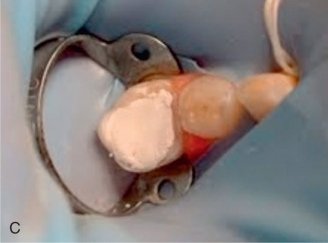

Sealing the Tooth

• Filling the tooth with a biocompatible material to prevent reinfection.

• Placing a temporary or permanent crown for added protection.